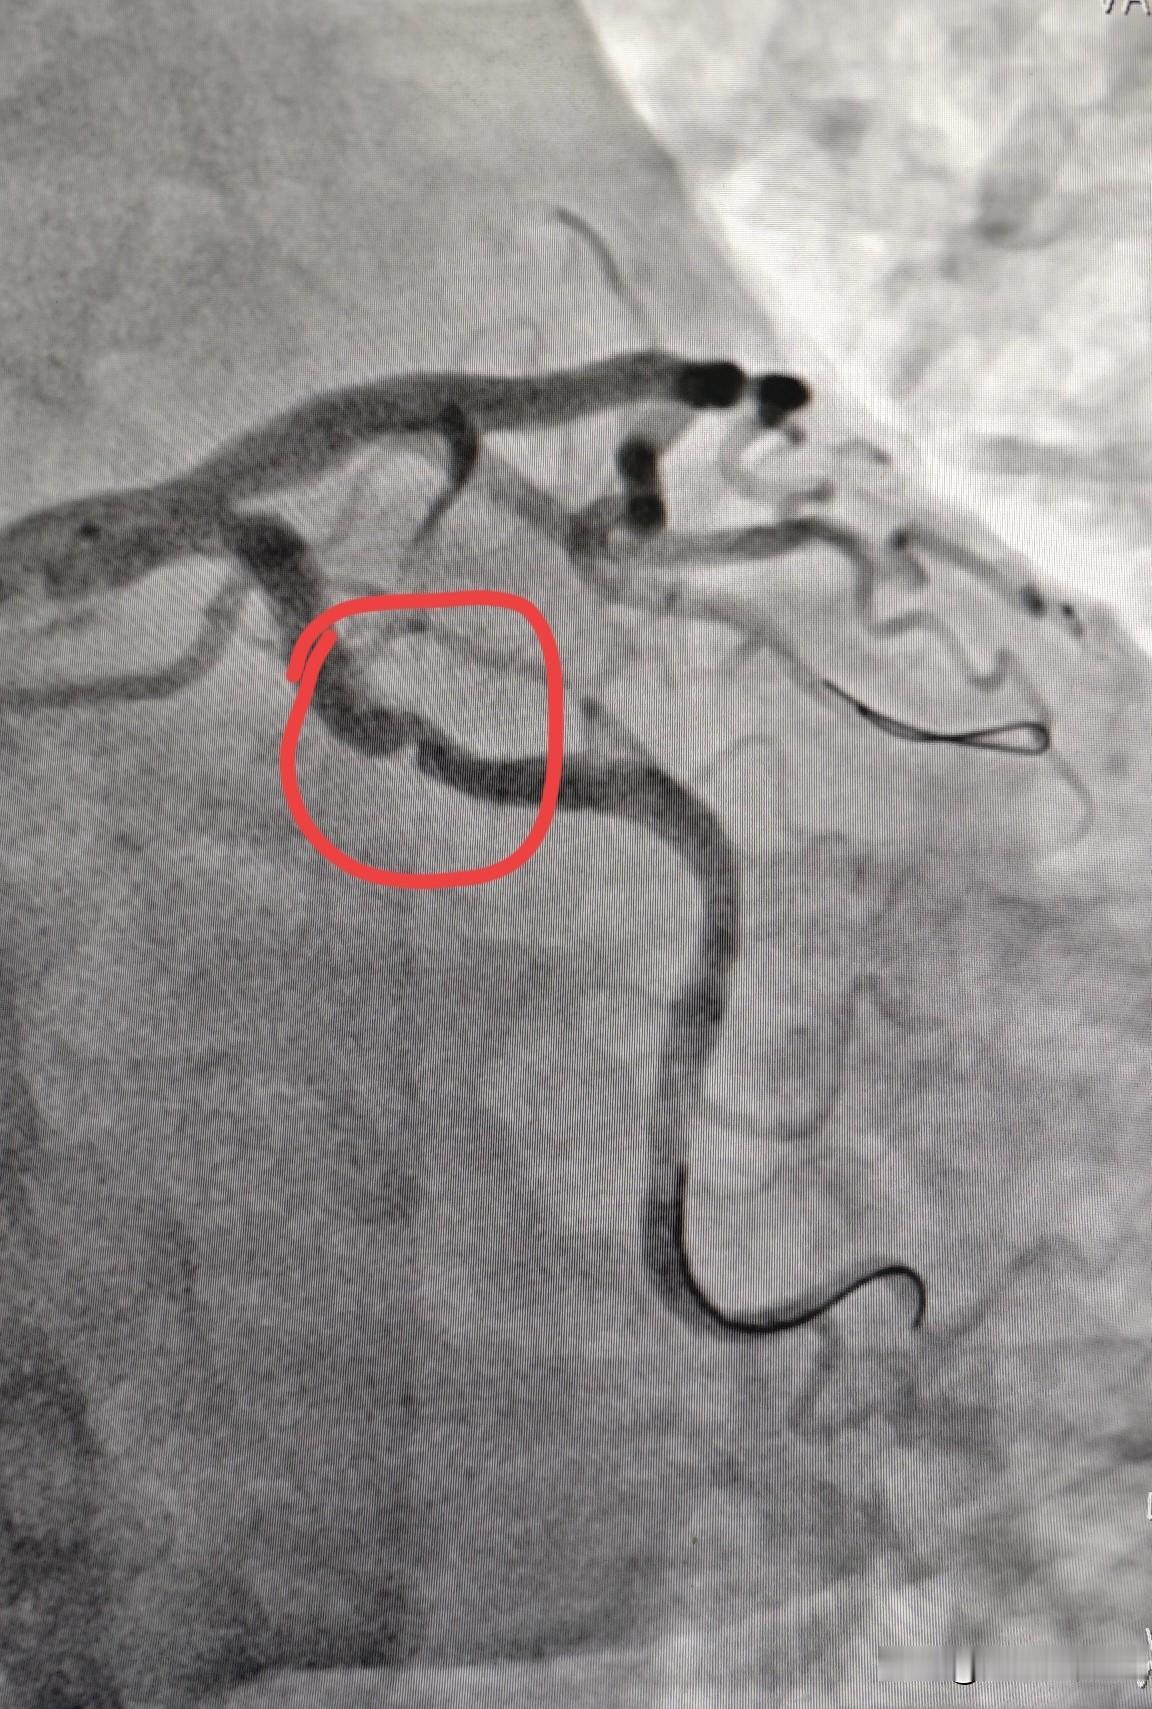

为什么说冬天是老年人的“一道坎”? 寒冬腊月,气温极低,遇上雨雪大风天气,气温骤降,“寒潮”来袭,人体生理机制面临更大压力,对老年人来说,是一次严峻的考验和挑战。 一般上了年纪的老年人,大多数人都常伴有高血压、高血糖、高血脂、冠心病、糖尿病、慢性阻塞性肺疾病、中风等基础疾病,寒冷的冬季,特别是天气变化异常的时候,最易导致这些疾病急性发作和加重,使得老年人在寒冬腊月的时候,成为他们需要格外小心,格外警惕的“健康关卡”。 所以说,冬天是老人的最为厉害的“一道坎”,面临着严峻的生死攸关的考验和挑战,过去农村在寒冬腊月之季,是老年人离世最多的时候,就足以说明这个问题。 那么,冬季老人最容易诱发的危险疾病有哪些呢? 冬季高发危险的疾病,有高血压、脑梗、心梗、冠心病、心绞痛、糖尿病、慢性阻塞性肺疾病、中风、猝死等重大基础疾病。 这些疾病,老年人在寒冷的冬天尤其要警惕,随着年龄的逐渐增长,老年人的身体器官功能逐渐的快速的衰退,衰老虚弱的身体,体温调节和耐寒能力,同样逐渐下降,加上老年人的饮食习惯的改变,营养不足,免疫力下降等,这些疾病易在冬季被诱发或加重,使冬季患病率,有明显高于年轻人的现象出现,是老人在冬季最为严峻的“一道坎”。 下面列举一些老年人在冬季最容易被诱发和加重的,需要特别注意的7个种类的疾病: ①心脑血管类疾病:是冬季老年人的头号健康杀手,是最为严重的威胁和挑战。 ②呼吸道类疾病:是老年人最容易患流感和肺炎的高发期频发期。 ③骨关节类疾病:老年人的“老寒腿”,疼痛加剧,是最明显的症状。 ④肠胃类疾病:老年人易诱发消化不良和肠胃炎,是冬季多发期。 ⑤意外摔倒:天气寒冷,身体灵活度低,老年人容易摔倒,易引发骨折及系列并发症。 ⑥皮肤疾病:老年人在冬季,容易引起皮肤干燥、瘙痒,甚至皲裂。 ⑦下肢静脉血栓:冬季寒冷,老年人会产生畏冷的惰性,久坐不动是常态,易藏隐患。 以上是本人观点,如有不妥,请大家在留言区中留下你宝贵的意见并积极参与评论。 探寻人工智能冬天健康小常识